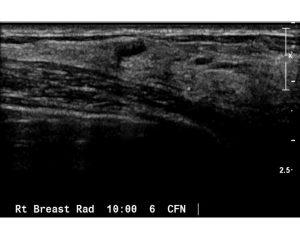

This course explores the use of screening breast ultrasound as a supplemental tool for detecting mammographically occult breast cancers, particularly in women with dense breast tissue. It covers scanning techniques, identifying benign and malignant masses, and the role of ultrasound in breast cancer detection. Learn about cysts, malignancies, and post-operative scars, along with the limitations and advantages of ultrasound compared to mammography. Ideal for radiologists and sonographers, this course emphasizes meticulous scanning and image interpretation for accurate diagnosis.

to describe the scanning technique of screening breast ultrasound

to discuss the ultrasound findings of cystic and solid breast masses